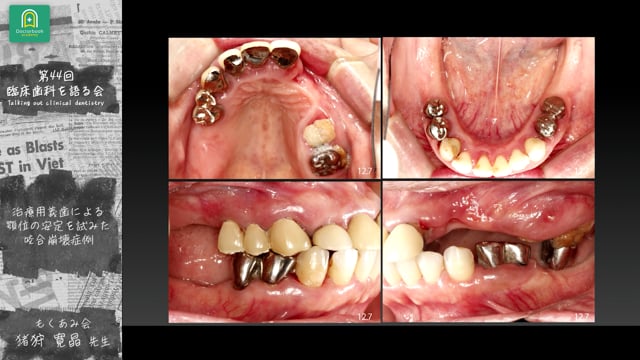

震災後に来院した55歳女性患者に対し、残存歯の保存を最大限に考慮した治療計画を実践。

治療用義歯を用いて咬合を確保し、段階的な咬合再構築とプロビジョナル調整を行うことで、上下的偏在を抑制し安定した咬合を獲得。

9年経過後も良好な機能維持を確認し、治療用義歯の活用と患者との情報共有が咬合再建成功の鍵であることを示しました。

咬合崩壊症例の補綴設計を実症例で解説。治療用義歯を用いた段階的咬合再構築と9年経過を報告する猪狩先生の発表。再生する